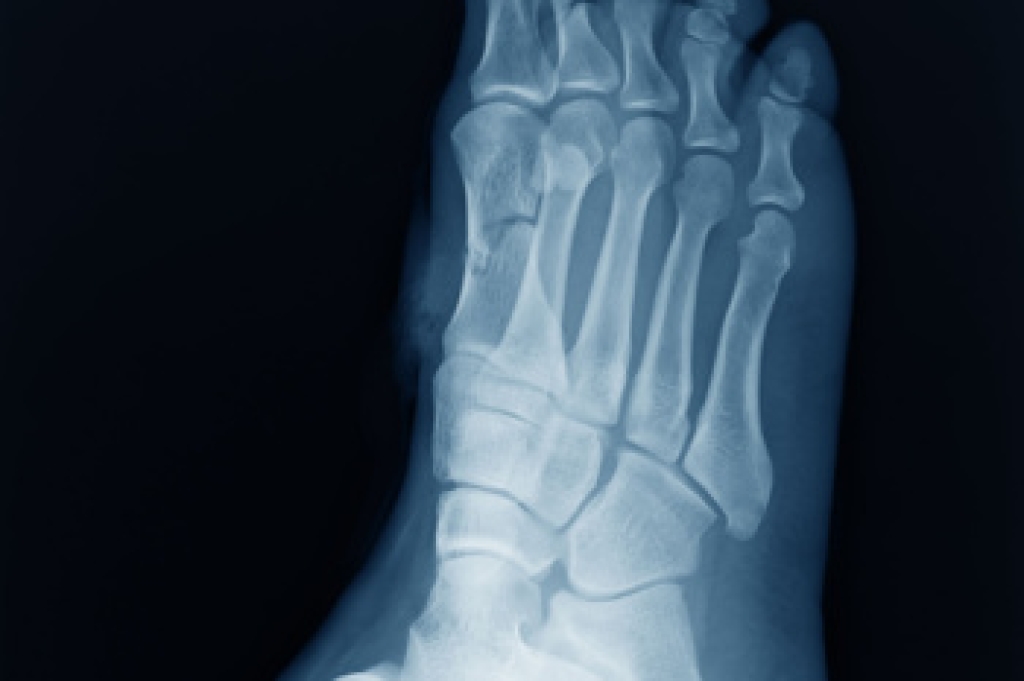

A foot stress fracture is a small crack in the bone caused by repetitive force or overuse rather than a sudden injury. Common causes include high-impact activities, wearing improper footwear, or a sudden increase in physical activity. Symptoms may involve pain that worsens with movement, swelling, and tenderness in the affected area. Risk factors include weak bones, poor conditioning, and inadequate rest. A podiatrist can diagnose a stress fracture through imaging tests and a physical examination, then create a personalized treatment plan to promote healing and prevent further injury. If you have persistent foot pain, it is suggested that you contact a podiatrist who can accurately diagnose and treat what may be going on.

Stress fractures are the result of repetitive force being placed on the bone. Since the lower leg and feet often carry most of the body’s weight, stress fractures are likely to occur in these areas. If you rush into a new exercise, you are more likely to develop a stress fracture since you are starting too much, too soon. Pain resulting from stress fractures may go unnoticed at first, however it may start to worsen over time.

To figure out the cause of foot pain, podiatrists utilize several different methods. This can range from simple visual inspections and sensation tests to X-rays and MRI scans. Prior medical history, family medical history, and any recent physical traumatic events will all be taken into consideration for a proper diagnosis.